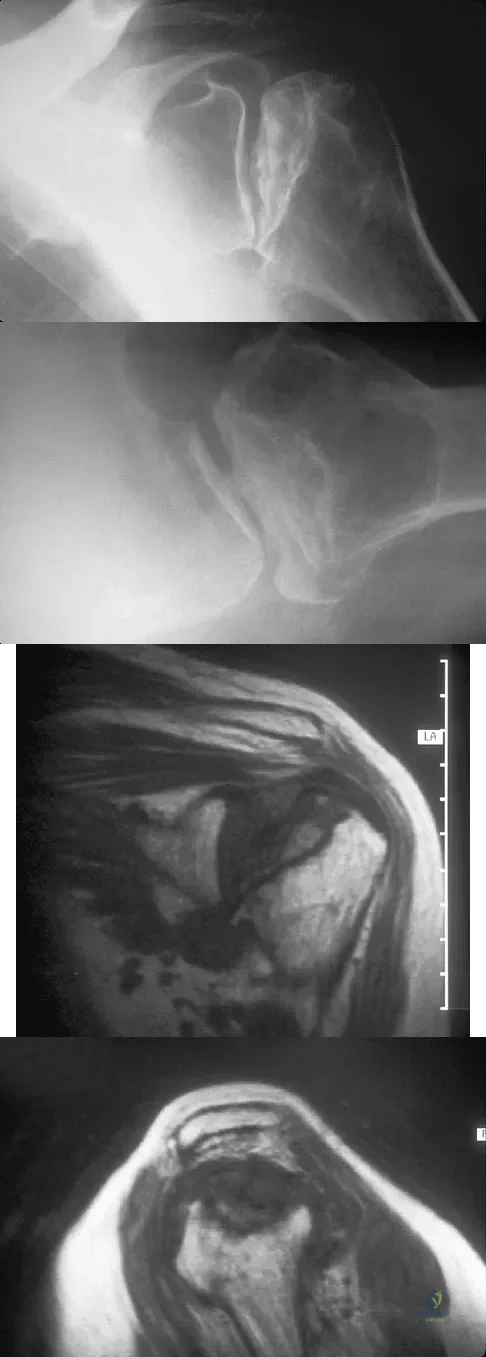

Question 69

A 55-year-old woman with a 15-year history of systemic lupus erythematosus has had left shoulder pain for the past 3 months. She reports that the pain has grown progressively worse over the past few months, and her shoulder function is severely limited. She is presently being treated with azathioprine and has used corticosteroids in the past. AP and axillary radiographs are shown in Figures 19a and 19b, and MRI scans are shown in Figures 19c and 19d. Which of the following forms of management will yield the most predictable pain relief and return of shoulder function?